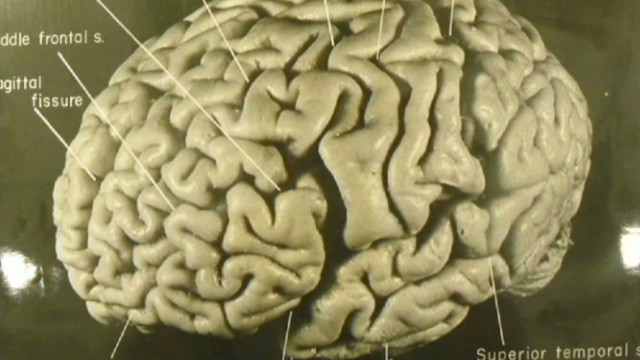

Https www alamy com a specimen of nobel physicist albert einsteins brain is seen in a glass slide at an exhibition at the wellcome collection in london march 27 2012 weve pickled it dessicated it drilled it mummified it chopped it and sliced it over centuries yet as the most complex entity in the known universe the human brain remains a mysterious fascination with samples of albert einsteins preserved brain on slides and specimens from other famous and infamous heads such as the english mathematician charles babbage and notorious mass murderer william burke an exhibition opening in london this week image377121679 html (Dateityp jpg)

/https://www.thestar.com/content/dam/thestar/news/gta/2015/10/15/albert-einsteins-brain-continues-to-fascinate-in-hamilton/sandrawitelsonbrain004.jpg)

/https://www.thespec.com/content/dam/thespec/news/world/2013/10/11/physical-features-of-einstein-s-brain-befit-a-genius-for-the-ages/B821416769Z.1_20131011221826_000_GIP13D1V2.2_Gallery.jpg)

/https://www.thestar.com/content/dam/thestar/news/gta/2015/10/15/albert-einsteins-brain-continues-to-fascinate-in-hamilton/sandrawitelsonbrain006.jpg)